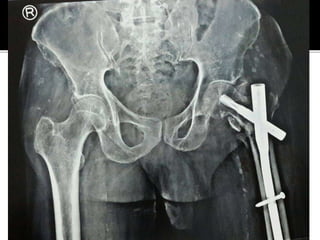

Failed

Subtrochanteric

fracture fixation

with broken DCS

and plate

After 51 days